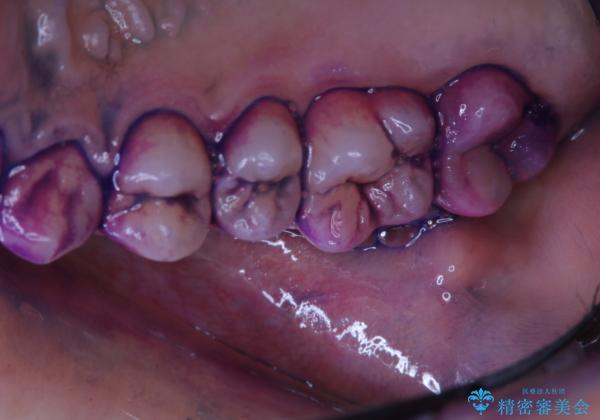

歯の染め出しとPMTCで口腔内ケア

- しばらく歯科でのメンテナンスを受けていないため、歯磨きのチェックとクリーニング希望とのことで来院されました。

染め出しをしてのブラッシング指導とPMTCを行いました。

染め出し液を使ってプラークを染め出すことにより、普段の歯みがきで磨き残している場所を目で確かめることができます。